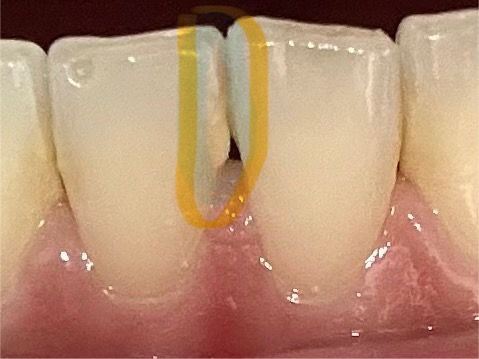

아래 앞니 하얀선과 모양이 옆에 것과 다릅니다

1. 왼쪽 아래앞니 모양이 일자가 아닙니다 ㅜㅜ 이건 이렇게 생긴이빨인걸까요 깨진건가요? 박거나 뭐 그런적이 없습니다. (노란 원)

2. 파란 원 안에 일자로 하얗습니다. 사진 상 잘 안나왔지만 다른 부분에 비해서 너무 하얗게 일자선이 있습니다. ㅠㅠ 이빨이 부식된건가요..?

• 2번 째 사진